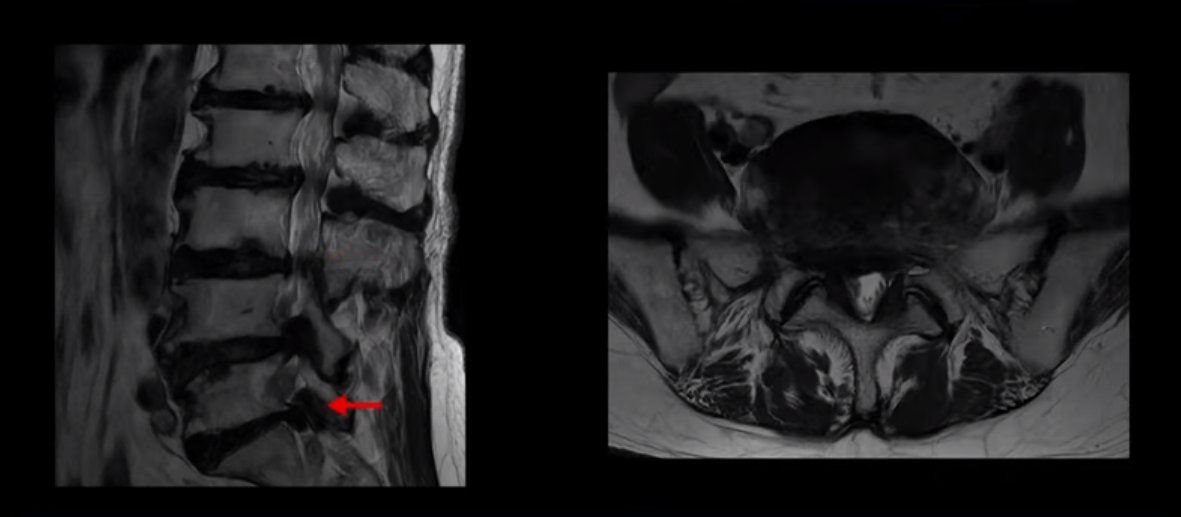

이 환자분은 MRI로 보면 허리 여러 마디가 신경이 매우 심하게 눌려 보이는 분입니다. 이분 MRI를 보면서 간단히 설명해 드린 후 어떻게 이렇게 신경이 심하게 눌린 환자분이 수술 없이 근육신경재활치료로 좋아질 수 있는지, 다리가 아파 걷지 못하는 환자가 어떻게 안 아프고 잘 걸을 수 있게 되는지, 10년 동안 괴로웠던 양 발의 시린 증상은 어떻게 사라질 수 있는지, 치료는 어떻게 하는지 자세히 설명 드리겠습니다.

MRI 보시면 (2-8) 허리의 5마디가 전부 다 심하게 퇴행되어 있습니다.

5마디 전부 다 심한 중심성 협착이 있습니다.

1번 2번,

2번 3번,

3번 4번,

4번 5번,

5번 6번

이렇게 모두 다 심하게 막히는 경우는 드문데요. 또한 오른쪽, 왼쪽 신경이 빠져나가는 추간공도 다 심하게 막혀있습니다.

오른쪽, 왼쪽 이렇게 신경 구멍들이 다 좁아지고 신경이 눌리니까 양쪽 다리가 발바닥까지 아파서 걷기 어렵고 양쪽 발이 10년 넘게 시린 겁니다. 당연히 수술해서 눌린 신경을 풀어줘야 한다고 들으셨는데요. 이런 환자분을 어떻게 수술 없이 치료할까요? 지금부터 설명해 드립니다.